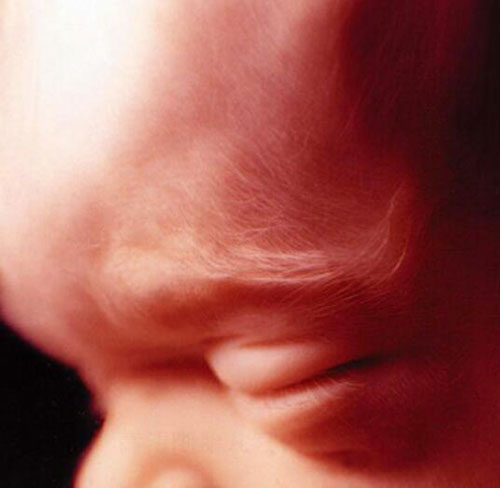

Thai nhi đang ngủ trong bụng mẹ, mắt lồi ra, nhằm nghiền.